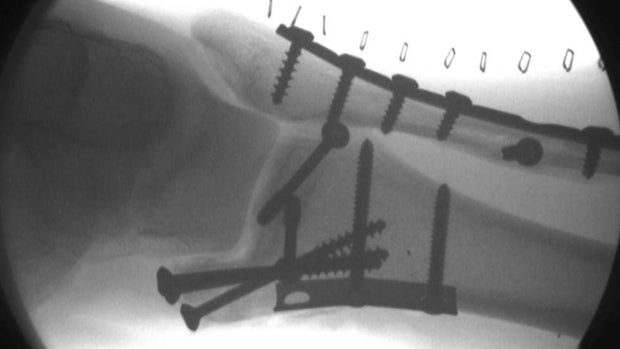

A CT-scan revealed a "calcified foreign body" in the child's left ear canal (scan pictured above). But what could it be?